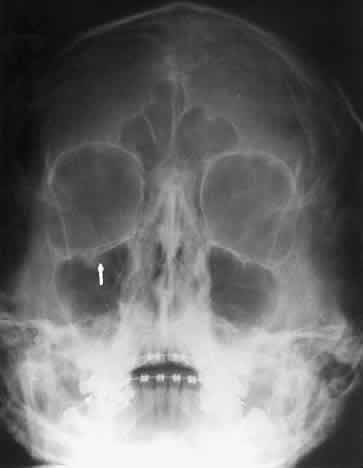

CALDWELL PROJECTION

In 1918 the evaluation of the frontal and ethmoid sinuses prompted Caldwell9 to describe a projection (Fig. 3) that eliminates the superimposition of the sphenoid bone on these paranasal sinuses. The patient is positioned with both the nose and forehead against the x-ray cassette while the x-ray beam is directed downward 15 degrees to 23 degrees to the canthomeatal line.5,6,9 This orientation also projects the petrous bones inferior to the orbit, thus avoiding obscuration of the orbital structures. As in the Waters view, the Caldwell view is a posterior-anterior projection. This excellent view of the frontal and ethmoid sinuses also allows good visualization of the orbital rims, greater and lesser sphenoid wings, lacrimal gland fossa, medial orbital wall, and both the superior and inferior orbital fissures.10 The innominate line is prominent in this view and represents the depression on the temporal surface of the greater wing of the sphenoid bone where it forms the medial wall of the temporal fossa or lateral wall of the orbit. This innominate line can be straight, end with a medial right angle turn, or continue inferiorly to form the outline of the pterygoid plate.8 A lack of continuity of the innominate line suggests a fracture of the lateral orbital wall.

Fig. 3. A. Schematic showing positioning for a Caldwell projection. (CM, canthomeatal line; CR, central ray) B. Radiograph of a Caldwell projection. The petrous ridge is positioned at the orbital floor. Detail of the orbital floor and maxillary sinus is blocked. C. The radiograph is taken at a steeper angle so the petrous ridge is now positioned lower within the maxillary antrum. (a, frontal sinus; b, innominate line; c, inferior orbital rim; d, posterior orbital floor; e, superior orbital fissure; f, greater wing of sphenoid;g, ethmoid sinus; h, medial orbital wall; i, petrous ridge; j, zygomatic-frontal suture; k, foramen rotundum) (A; Rao VM, Gonzalez CF: Plain film radiography and polytomography of the orbit. In Gonzalez CF, Becker MH, Flanagan JC [eds]: Diagnostic Imaging in Ophthalmology, pp 1–7. New York, Springer Verlag, 1986)